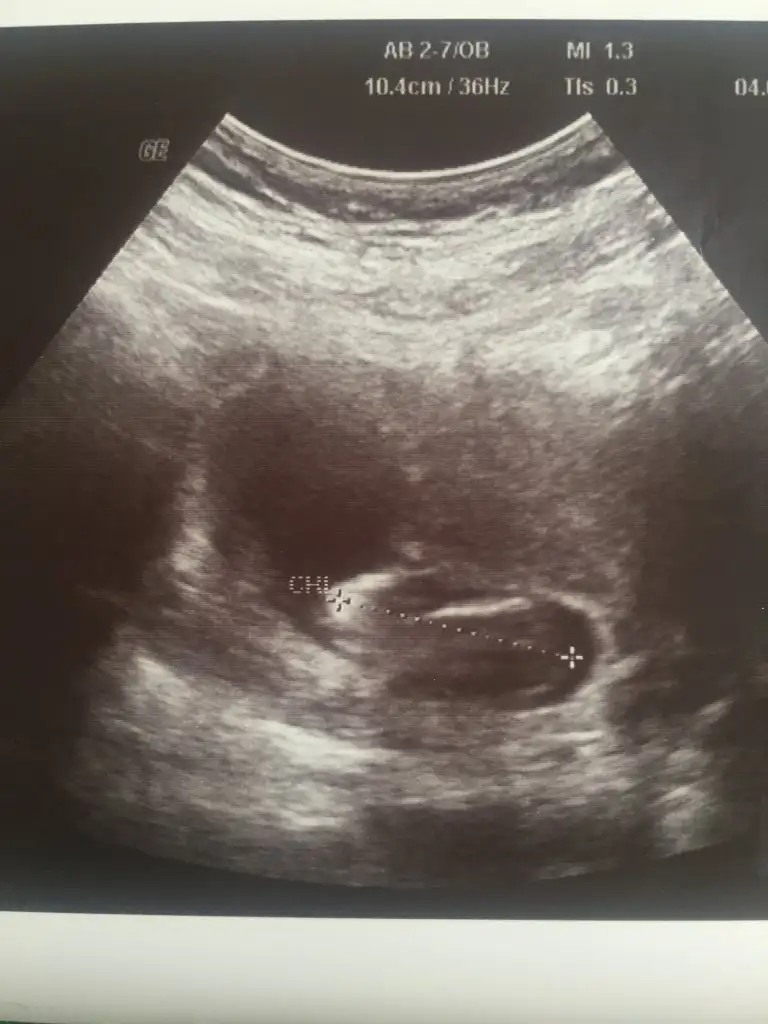

Kafa yapısı erkek gibi

Nub göremedim 11 yada 12 hafta usg paylaşın elinizde hangi usg varsa

13+6 olan usg varmı başka bunda net degil kafa yapısı tutmayada bilirO haftalara ait usg yok malesef tesekkurediyorum